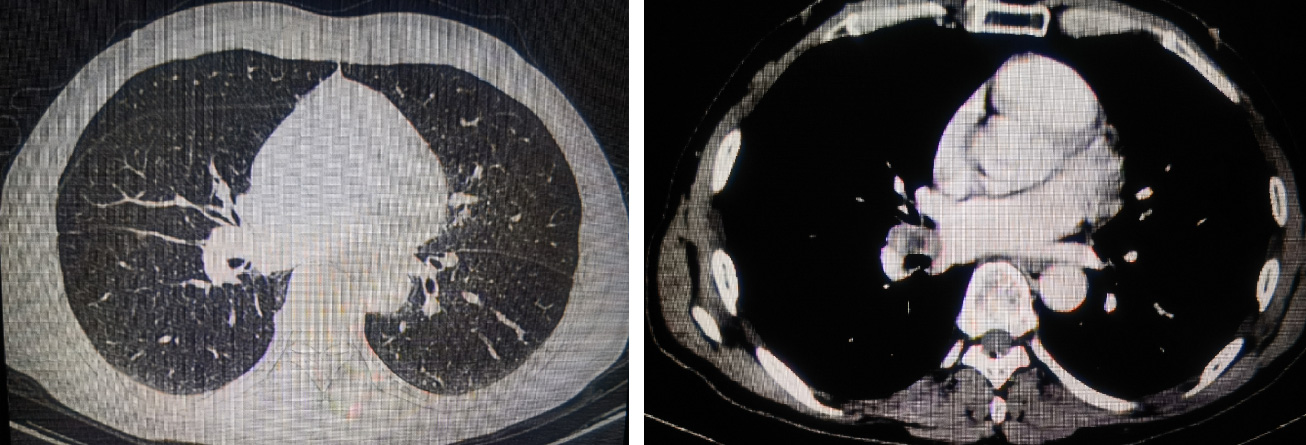

影像学检查

胸部CT:右中间支气管及右肺中叶、下叶支气管壁增厚并周围肿块形成,大小约4.4cmx3.3cm,密度不均,增强后强化不均,病变粘连邻近右肺门血管。右肺门及纵隔多发淋巴结显示,大者大小约1.3cmx0.9cm。

PET-CT:右中间支气管、右肺下叶支气管开口处、右肺中叶支气管开口处软组织增厚并一软组织肿块形成,伴代谢增高,符合肺癌征象,右肺下叶外基底段见结节影,代谢增高,倾向转移,纵隔4R、7组,右肺门多个代谢增高淋巴结,倾向肿瘤转移。

2、疗效评价:4周期新辅助治疗后复查胸部CT提示,右中间支气管及右肺中叶、下叶支气管壁增厚并周围软组织灶形成,较大层面大小约2.5cmx1.1cm(治疗前大小为4.4cmx3.3cm),病变粘连邻近右肺门血管。右肺门及纵隔多发淋巴结显示,短径均小于1.0cm。

基线CT

4周期新辅助治疗后CT